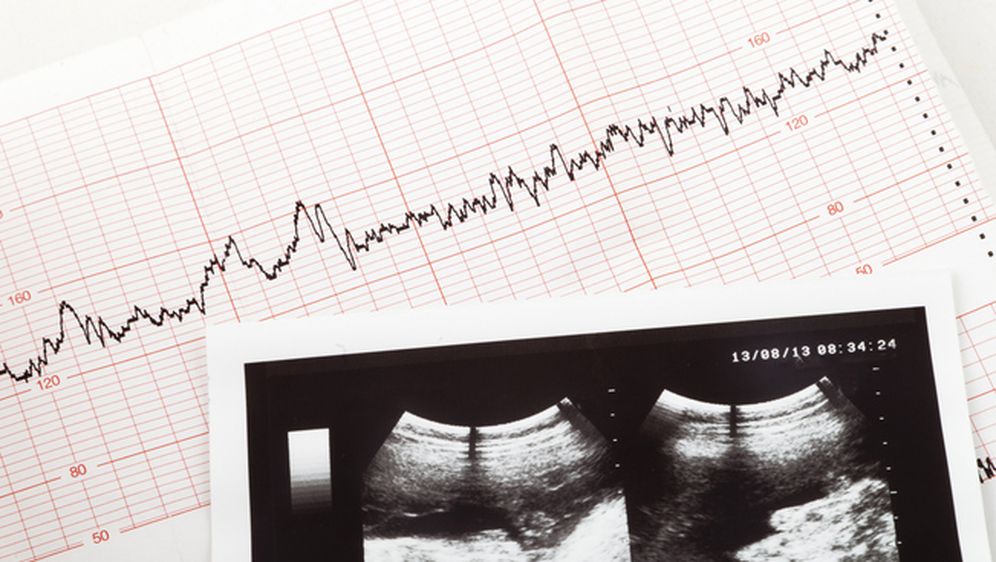

Ljudsko tijelo koristi nesvakidašnje strategije kako bi preživjelo neke vrlo rijetke zdravstvene prijetnje. Jedana takva strategija proizlazi iz fenomena trbušne trudnoće, gdje se oplođeno jajašce implantira i raste izvan maternice, što je situacija prepuna opasnosti i visokog rizika za majku.

U rijetkim slučajevima, ako fetus umre, majčino tijelo štiti se od infekcije kalcificiranjem ostataka fetusa, obavijajući ih kalcijem kako bi se formirao litopedij, ili takozvana "kamena beba". Prema starogrčkoj terminologiji, taj kalcificirani fetus predstavlja izvanredan zaštitni mehanizam ljudskog tijela.